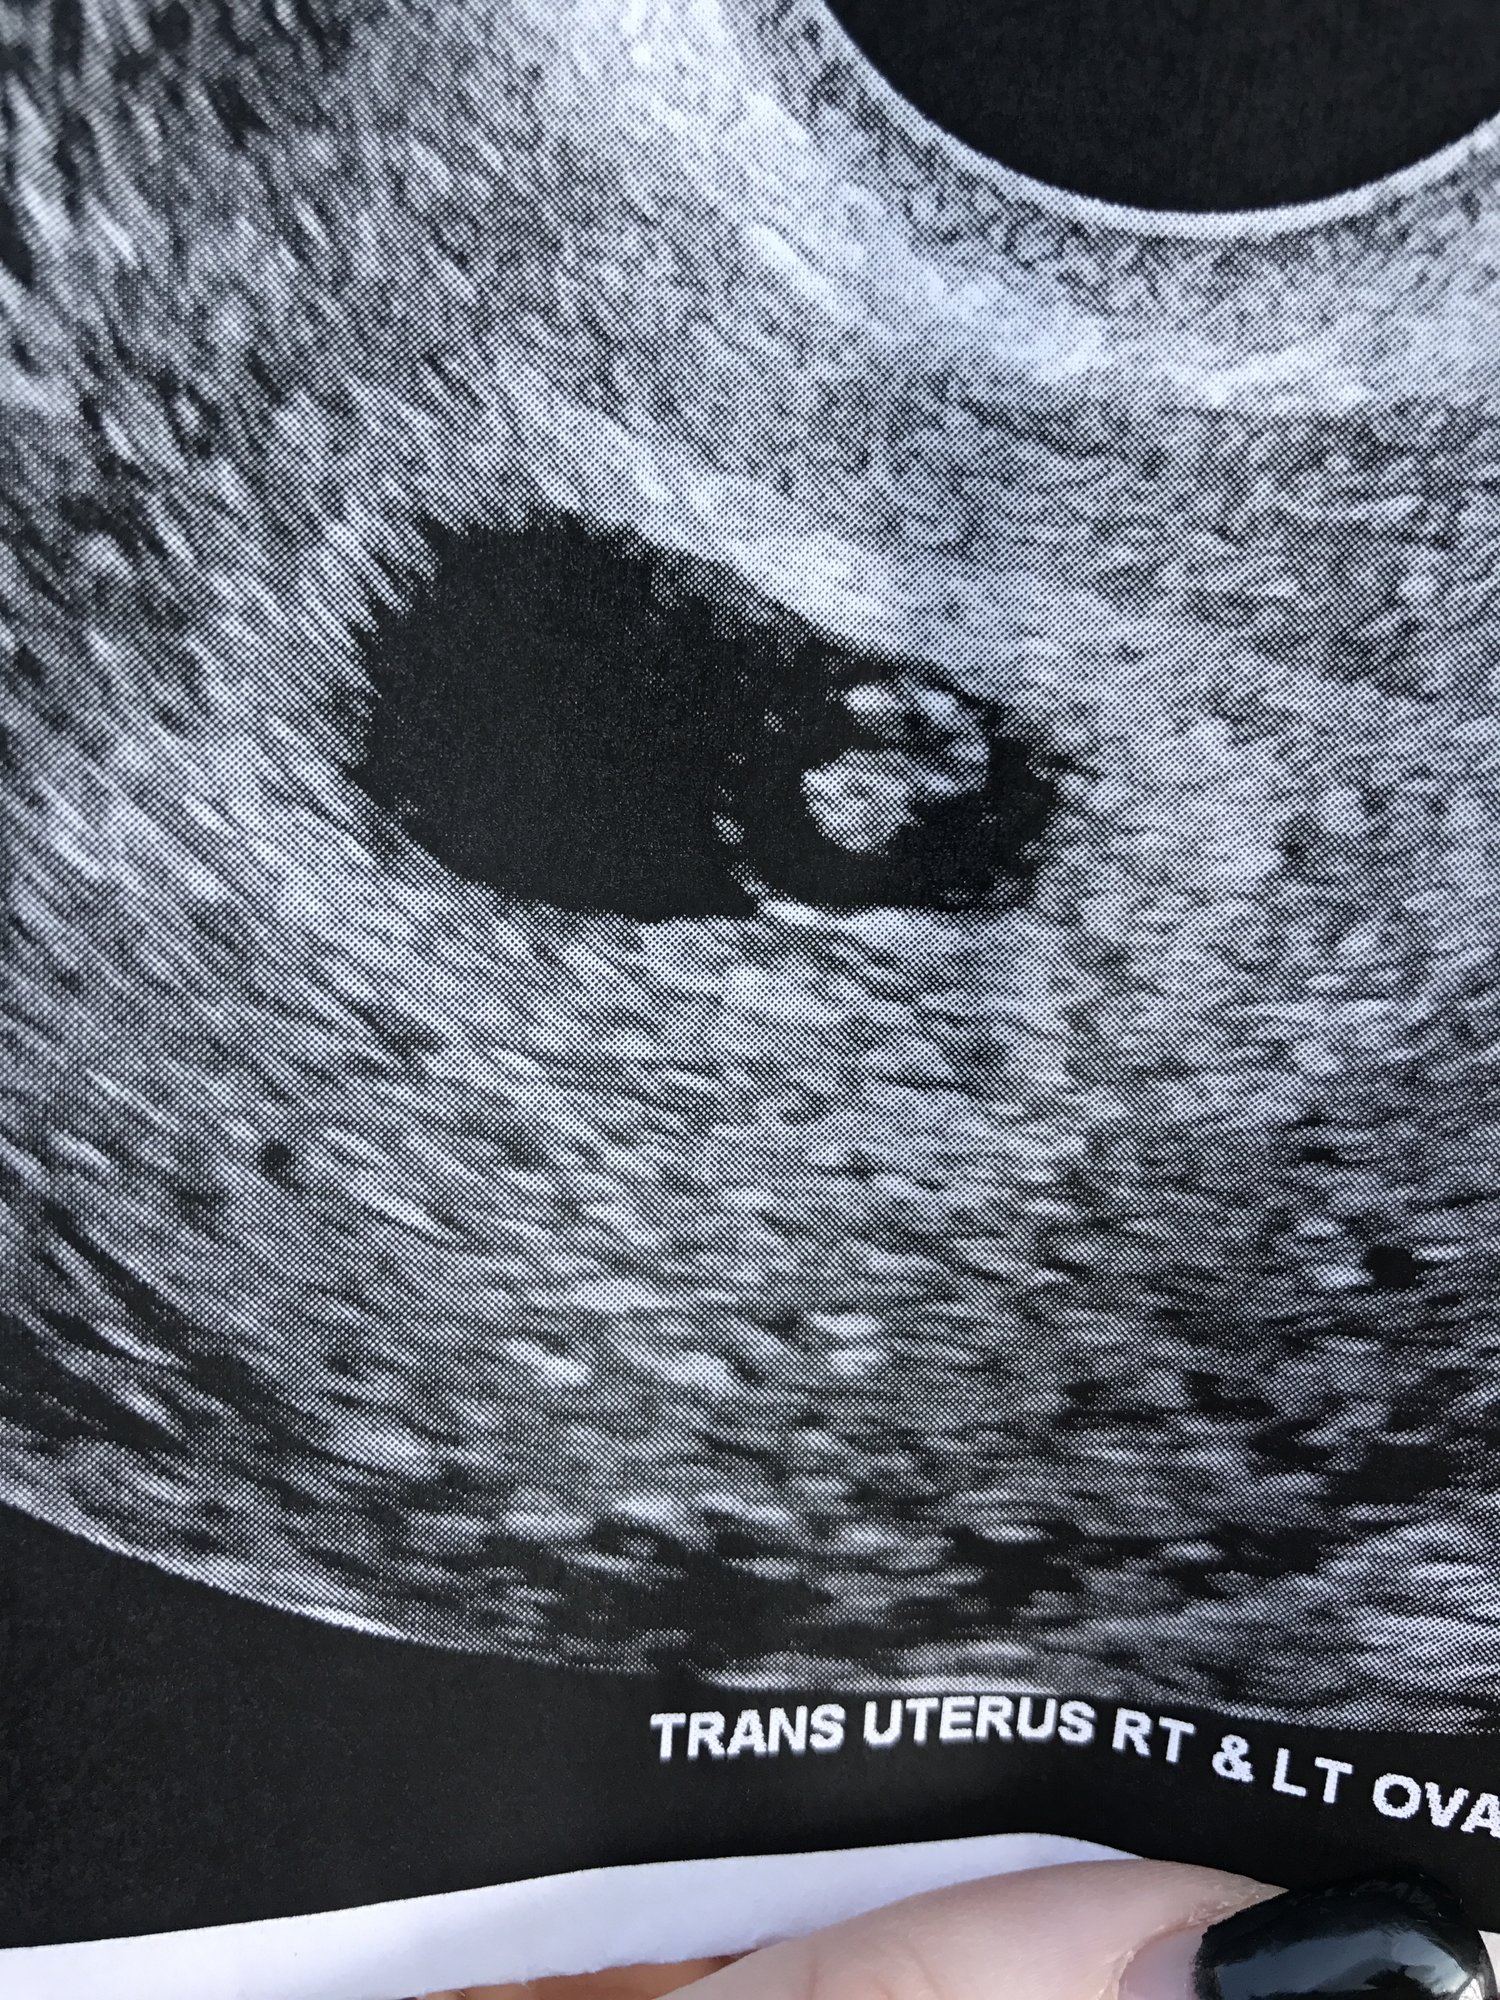

I had my second ultrasound today. The first was ten days ago and it measured me at five weeks with a yolk sac and gestational. Today it measured me at five weeks six days with a crown rump length which I didn't have last time. But no heartbeat

also there's another ring additional to my yolk sac and I have no idea what it is.. My hcg has been rising. But I feel like this is developing slow. I feel heartbroken as I've had two miscarriages. I feel like something is wrong with me.